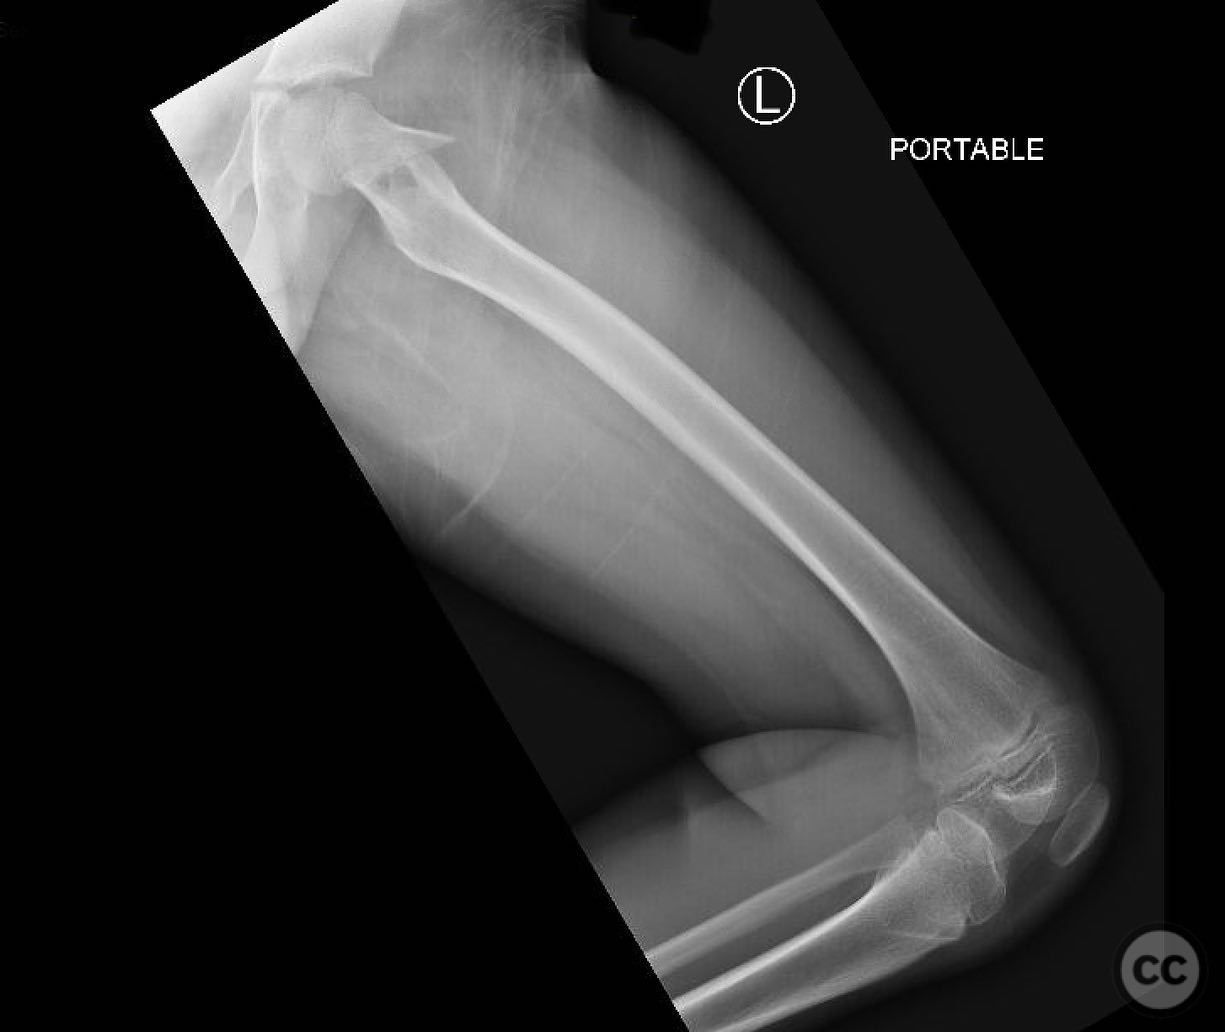

Clinical and radiological findings:  An 8-year-old boy fell approximately 15 feet from a treehouse, sustaining a displaced femoral neck fracture. There were no associated injuries to the head, spine, chest, or abdomen. The initial radiological assessment confirmed a displaced fracture of the femoral neck. Neurovascular examination was unremarkable.

Planning remarks:  The preoperative plan involved achieving a direct anatomic reduction and stable fixation of the femoral neck fracture. The surgical approach considered was a modified Smith-Petersen approach for optimal visualization and reduction, followed by a separate lateral approach for implant application.

Orthopaedic implants used:   Angle stable static device (specific brand not mentioned).